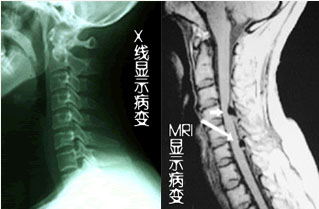

坐骨神经痛是指坐骨神经通路及其分布区的疼痛综合征。即疼痛位于臀部、大腿后侧、小腿后外侧和足外侧。按病因分为原发性和继发性坐骨神经痛。》》》文章看不懂,点击此处在线咨询专家

美国旋切消融术是美国旋切术和消融术两种技术的融合,美国旋切术是目前较成熟的治疗坐骨神经痛的微创方法之一。在影像增强设备的引导下,使用微创旋切器械,在脊柱的后外侧,通过皮肤穿刺到椎间盘内,在通过特殊的工作套管,建立手术通道。在已建立通道内,使用髓核旋切设备将突出髓核组织取出,达到治疗的目的。而消融术是指超氧消融术,以O2+O3混合物作为气态医疗物质在临床上应用,称为“超氧疗法”,在影像增强设备引导下,通过皮肤穿刺直达突出的髓核组织,在髓核组织内注射臭氧气体,使髓核组织脱水萎缩,达到降低椎间盘内压、溶解突出的髓核组织。